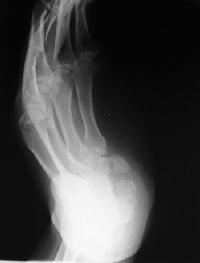

This chronically painful nonunion was not visible on PA, lateral and oblique films, but can be seen clearly on this supinated oblique hamate hook view:

and on this slightly different angle of the same view